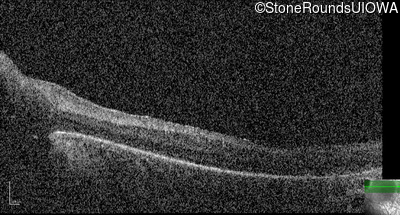

Optical Coherence Tomography - Right -

No Light Perception

Exemplar

Optical Coherence Tomography - Left -